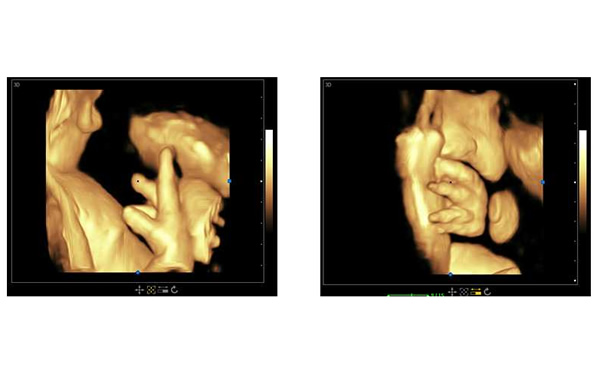

孕期B超檢查三個階段,大為醫(yī)療高端彩超孕期胎兒顯示

醫(yī)院用高端三維多普勒、4D成像技術(shù)的彩超可以參考大為醫(yī)療的高端彩超。